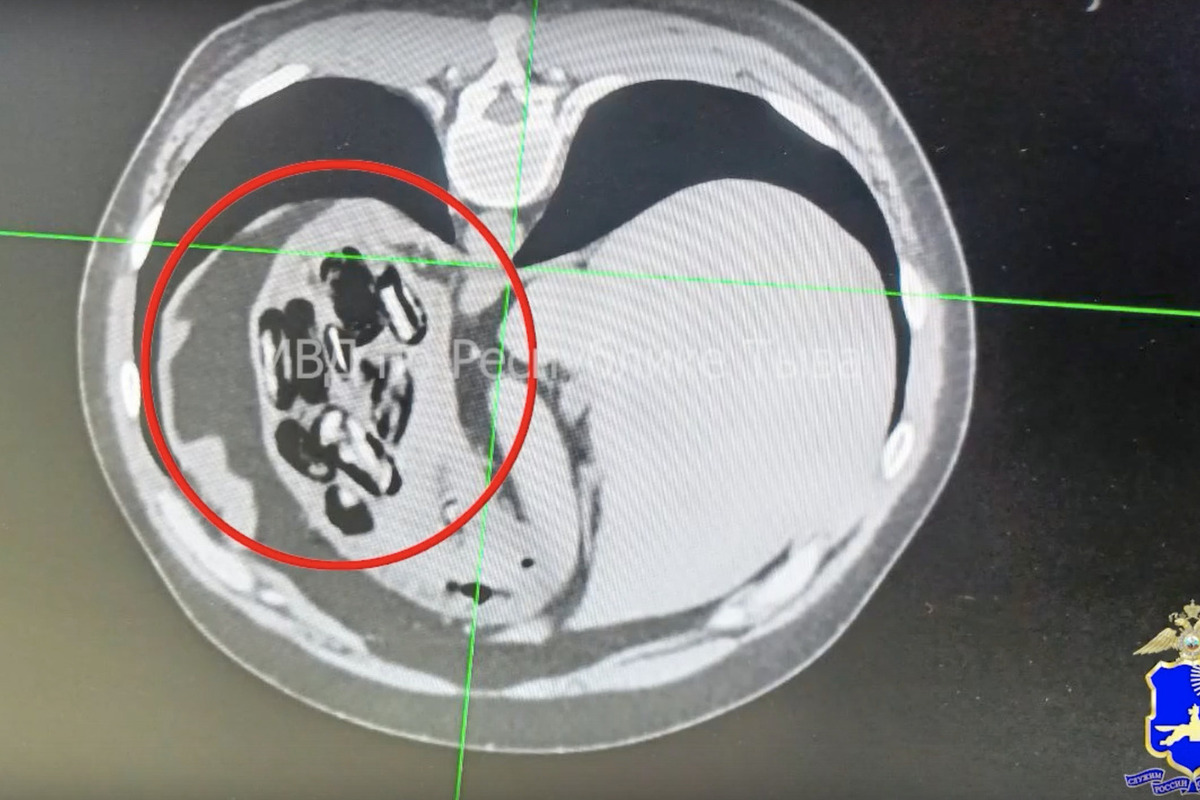

С согласия задержанного проведена компьютерная томография внутренних органов.

В результате и врачи выявили наличие в брюшной полости у мужчины многочисленных инородных тел. Из желудка путем опорожнения были извлечены 16 фрагментов. Это был  гашиш, общей массой 54,74 грамма. Задержанный гражданин намеревался перевезти указанное наркотическое средство в Сахалинскую область с целью последующего сбыта.